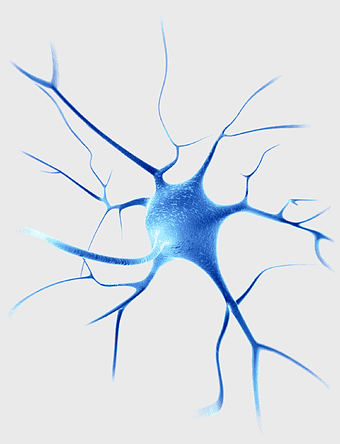

blue neuron cell, neuroscience gene therapy, spinal muscular atrophy research, electric blue dendrite, neural network structure, medical science illustration, human nervous system art -